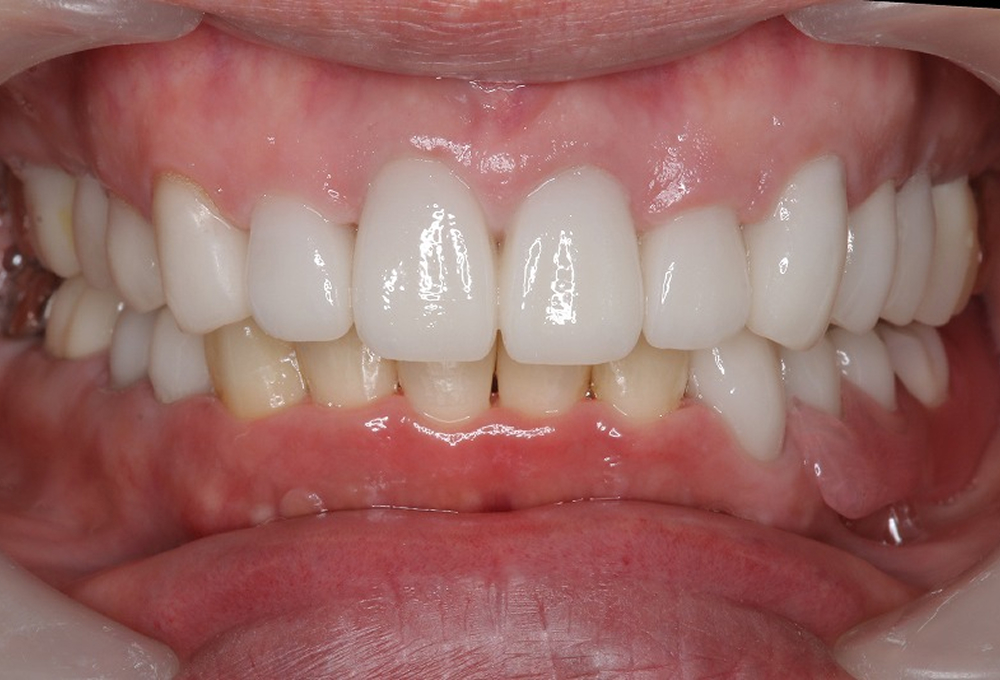

⑤矯正後補綴